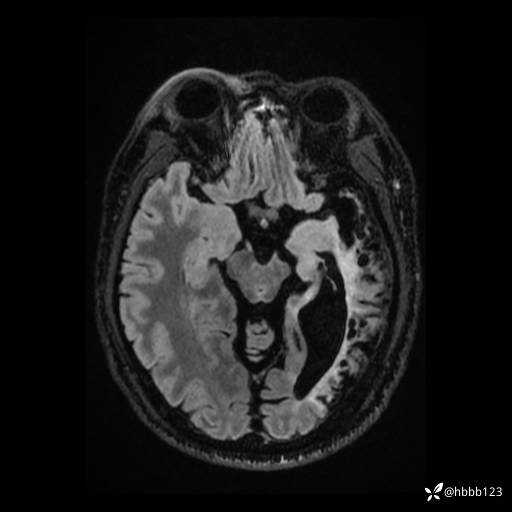

患者男,43岁。

简要病史:癫痫患者复诊,昨日发作5-6次,建议住院进一步治疗。

入院完善脑癫痫组合序列:

T2: